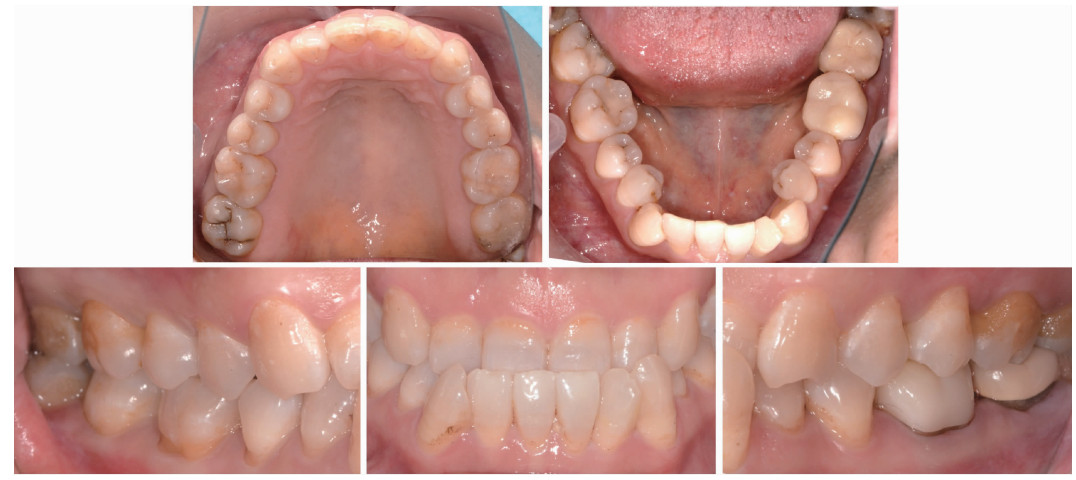

Figure 3

Intraoral images at 1-year follow-up"